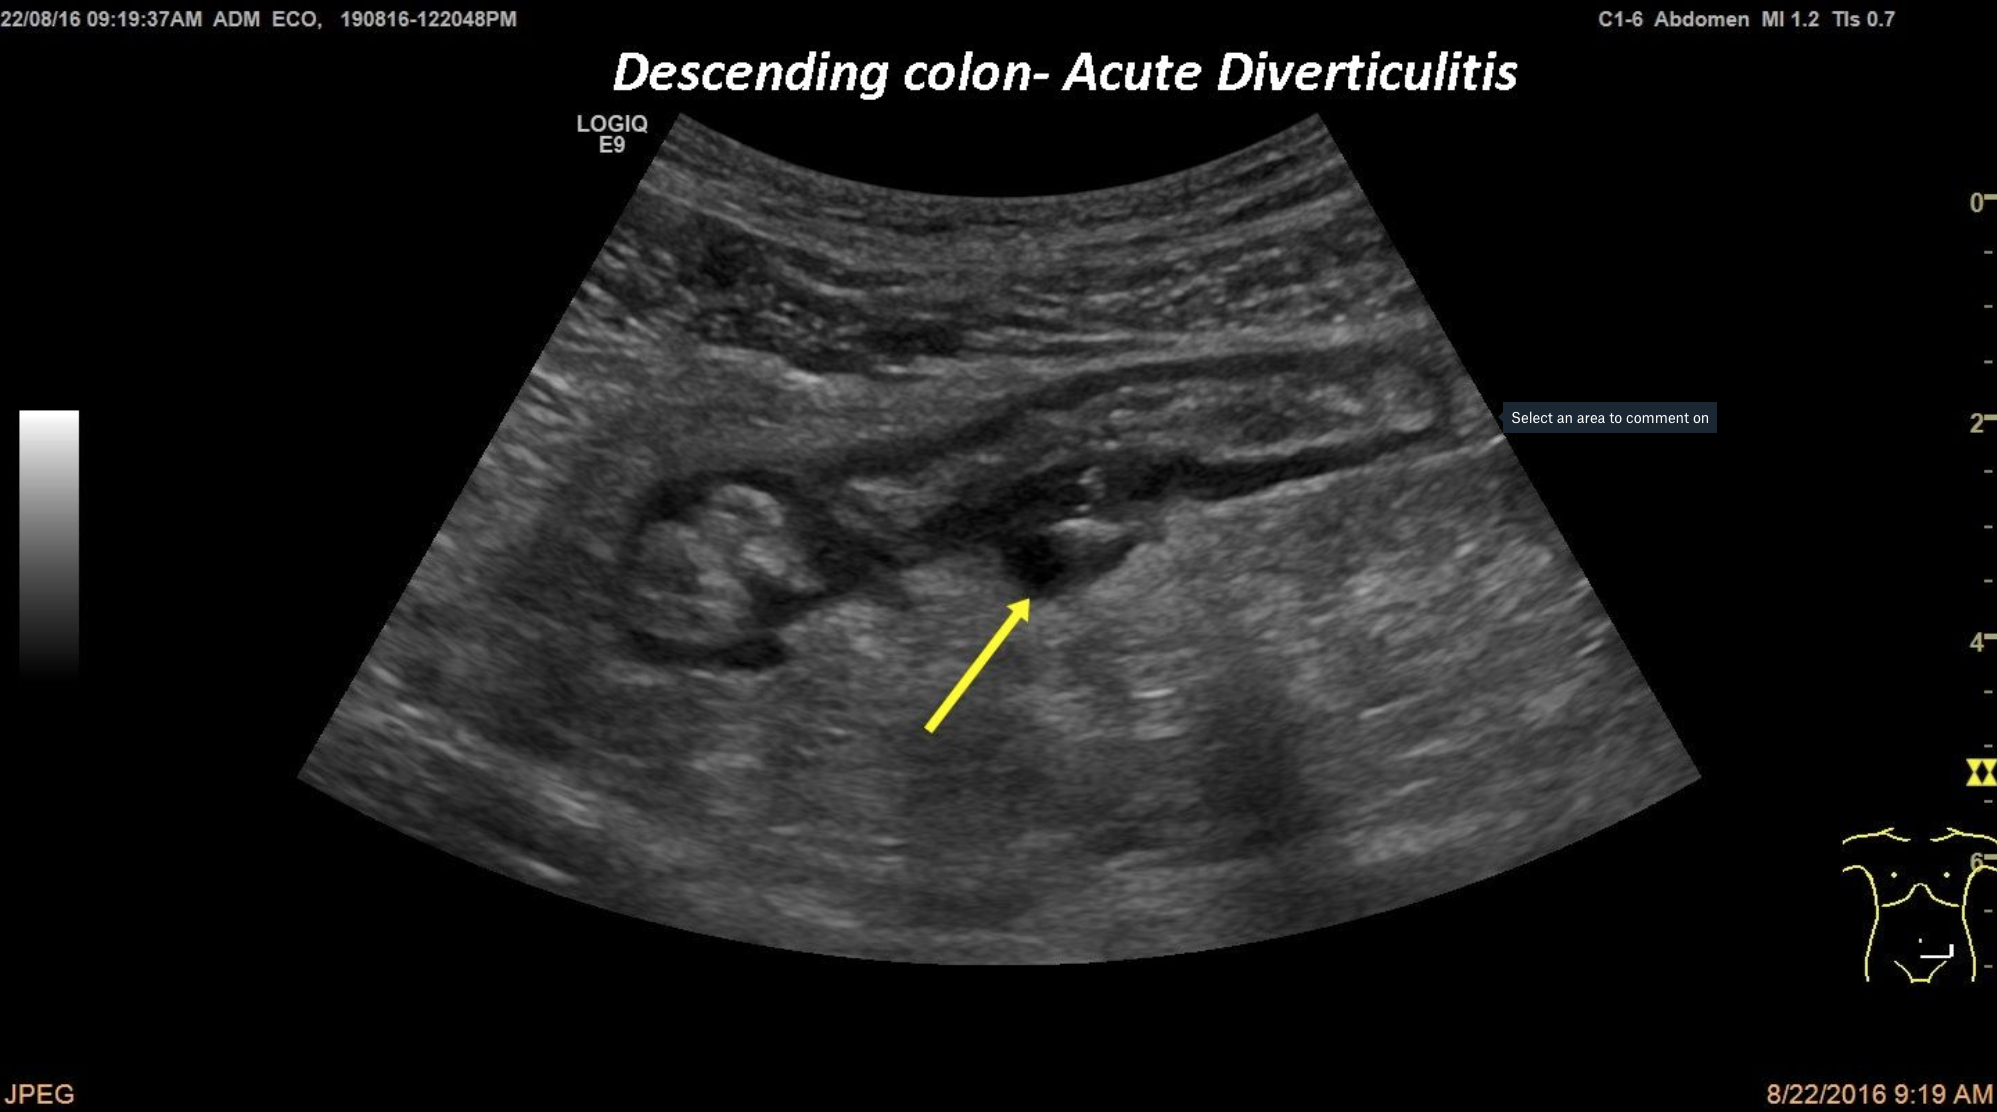

An 38 years old patient was brought into the emergency room with intense pain localised into the left lower quadrant. In this ultrasound section of the sigmoid colon, the arrow is pointing to the pro eminent diverticulum with signs of inflammation like the inhomogeneous aspect, wall thickening and the loss of the multi layer pattern.

Descending colon, acute diverticulitis, left lower quadrant